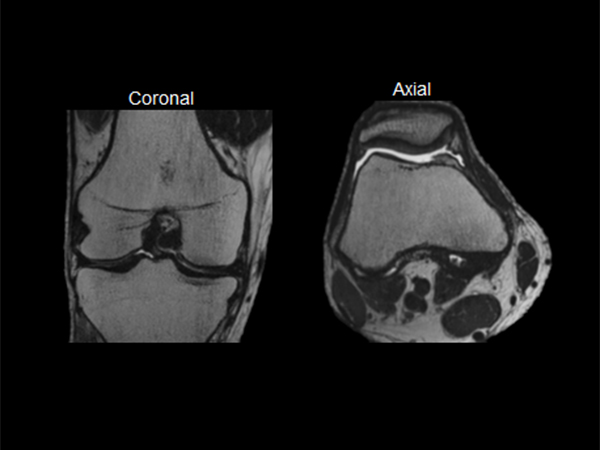

Knee imaging